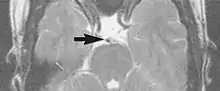

A motion artifact is one of the most common artifacts in MR imaging.[2] Motion can cause either ghost images or diffuse image noise in the phase-encoding direction. The reason for mainly affecting data sampling in the phase-encoding direction is the significant difference in the time of acquisition in the frequency- and phase-encoding directions.[1] Frequency-encoding sampling in all the rows of the matrix (128, 256 or 512) takes place during a single echo (milliseconds). Phase-encoded sampling takes several seconds, or even minutes, owing to the collection of all the k-space lines to enable Fourier analysis. Major physiological movements are of millisecond to seconds duration and thus too slow to affect frequency-encoded sampling, but they have a pronounced effect in the phase-encoding direction. Periodic movements such as cardiac movement and blood vessel or CSF pulsation cause ghost images, while non-periodic movement causes diffuse image noise (Fig. 1). Ghost image intensity increases with amplitude of movement and the signal intensity from the moving tissue. Several methods can be used to reduce motion artifacts, including patient immobilisation, cardiac and respiratory gating, signal suppression of the tissue causing the artifact, choosing the shorter dimension of the matrix as the phase-encoding direction, view-ordering or phase-reordering methods and swapping phase and frequency-encoding directions to move the artifact out of the field of interest.[1]

Flow can manifest as either an altered intravascular signal (flow enhancement or flow-related signal loss), or as flow-related artifacts (ghost images or spatial misregistration). Flow enhancement, also known as inflow effect, is caused by fully magnetised protons entering the imaged slice while the stationary protons have not fully regained their magnetization.[1] The fully magnetized protons yield a high signal in comparison with the rest of the surroundings. High velocity flow causes the protons entering the image to be removed from it by the time the 180-degree pulse is administered. The effect is that these protons do not contribute to the echo and are registered as a signal void or flow-related signal loss (Fig. 2).[1] Spatial misregistration manifests as displacement of an intravascular signal owing to position encoding of a voxel in the phase direction preceding frequency encoding by time TE/2.The intensity of the artifact is dependent on the signal intensity from the vessel, and is less apparent with increased TE.[1]